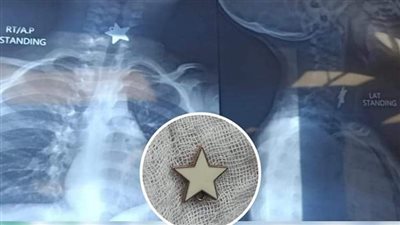

الرعاية الصحية: إنقاذ حياة طفل ابتلع قطعة معدنية بمستشفى المبرة في بورسعيد